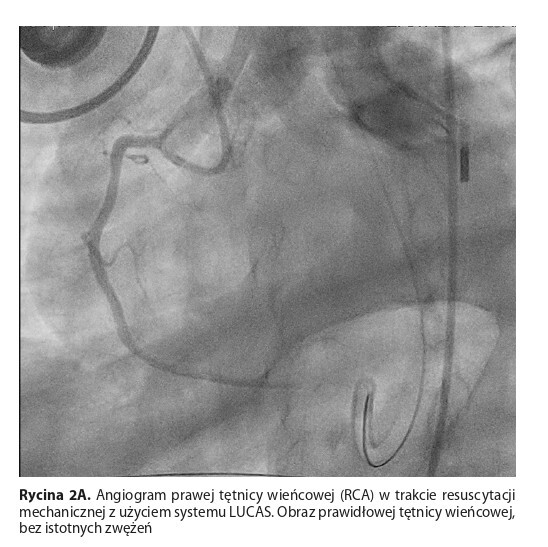

The case of a 65-year-old man is presented who experienced anginal pain for the first time in his life during daily activities. On his way to the hospital, shortly after entering the building, he suffered SCA due to ventricular fibrillation. Thanks to the immediate intervention of the hospital staff, the use of

the LUCAS mechanical chest compression system, and rapid transport to the catheterization lab it was possible to restore sinus rhythm after multiple defibrillations and successful angioplasty of an occluded left anterior descending artery (LAD). Despite the implementation of advanced treatments, including intra-aortic balloon pump (IABP), continuous renal replacement therapy (CRRT), and extracorporeal membrane oxygenation (ECMO), the patient died due to progressing multi-organ failure.